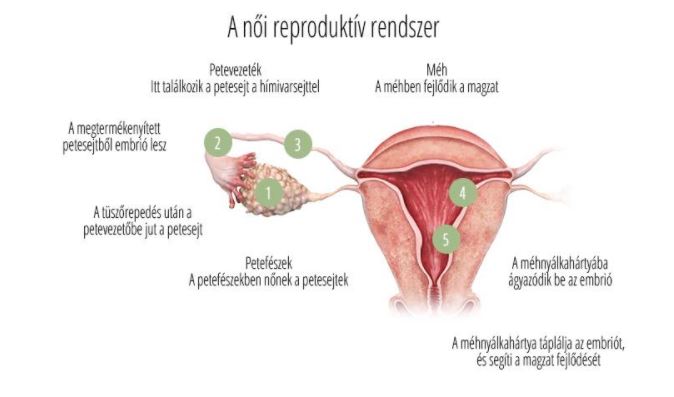

A méh nyálkahártyáját, az úgynevezett endometriális sejtek alkotják, mely, ha nem ágyazódik be embrió, hormonális hatásra leválik, és a nő menstruál.

A méh nyálkahártyáját, az úgynevezett endometriális sejtek alkotják, mely, ha nem ágyazódik be embrió, hormonális hatásra leválik, és a nő menstruál.